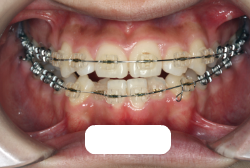

今回の患者様の場合は、「外科」も「小臼歯抜歯」も拒否されましたので、歯科矯正用アンカースクリュー(以下 アンカースクリュー)を用いて、下顎の歯列全体を後方に下げるという方法を取りました。

治療中の写真で、アンカースクリューより歯を後ろへ牽引しているのがお分かりいただけるかと思います。牽引を1年ほど続け、途中補助的に上下にゴムをかける(これを顎間ゴムと言います)手法なども追加し、全体で21ヶ月で治療を終えることが出来ました。

結局歯の本数を減らすことなく、すべてご自分の歯を残して、正しい配列と噛み合わせにすることができました。凸凹があまりひどくないため、簡単そうに見えると思いますが、このケースの初診の状態を見ると、熟練の矯正歯科医でも悩みのつきないケースです。まして、外科も出来ない、抜歯もイヤ、と言うことになると、従来の方法では治療不可能と考えられるのですが、アンカースクリューを使うことで最近は不可能が可能となってきました。